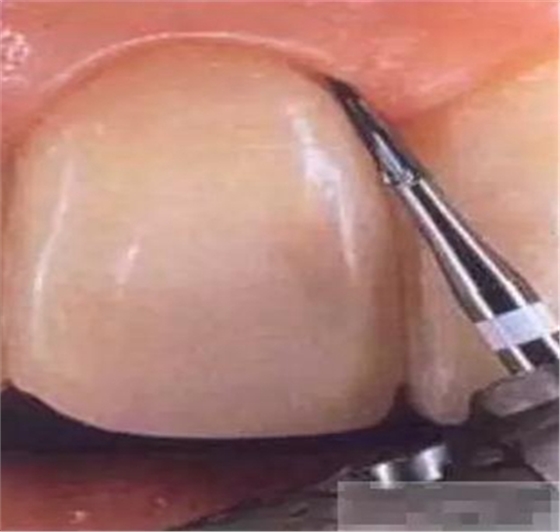

【基牙預(yù)備】樹(shù)脂貼面平齊牙齦邊緣是最佳設(shè)計(jì),或者使用齦上邊緣。

粘結(jié)面涉及的釉柱越多粘接力越強(qiáng)。Dr.Vanini的設(shè)計(jì)是,后牙區(qū)預(yù)備平面肩臺(tái),前牙區(qū)預(yù)備成淺凹肩臺(tái)(成年患者的肩臺(tái)區(qū)面積較小,年輕患者較大),鄰面和腭側(cè)預(yù)備平面肩臺(tái)。

樹(shù)脂貼面平齊牙齦邊緣是最佳設(shè)計(jì),或者使用齦上邊緣

制備量問(wèn)題:1-2種顏色,需要0.3mm牙體預(yù)備

3-5種顏色,需要0.5mm牙體預(yù)備 5種以上的顏色,需要0.7-1.0mm牙體預(yù)備

釉質(zhì)邊緣要用橡皮輪拋光

拋光可以去除懸釉。這樣經(jīng)過(guò)車針打磨過(guò)的釉質(zhì)表面會(huì)更加均一,形成良好的邊緣封閉。